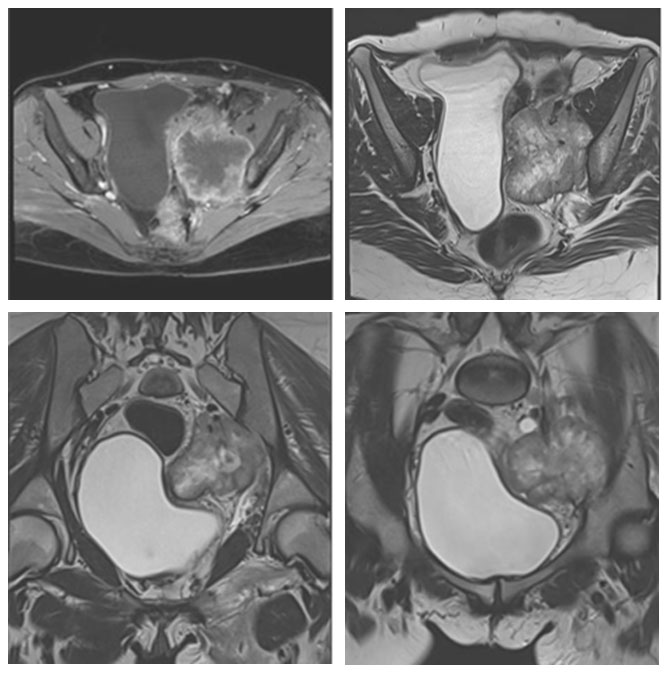

Ameliyat Öncesi: MR’da sol sakroiliak eklem seviyesinde düzensiz sınırlı içinde gaz gölgesi olan ve mesaneyi iten büyük yumuşak doku kitlesi görülmekte

MR’da sol sakroiliak eklem seviyesinde düzensiz sınırlı içinde gaz gölgesi olan ve mesaneyi iten büyük yumuşak doku kitlesi görülmekte